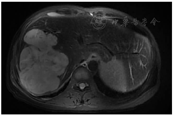

患者女性,44岁,2013年发现肝恶性占位,在福建省立医院行手术治疗,术后病理诊断为"肝脏炎性假瘤样滤泡树突状细胞肉瘤(follicular dendritic cell sarcoma,FDCS)",术后定期随访至2018年未见复发。2021年5月影像学检查再次发现肝占位性病变,6月29日患者就诊于海军军医大学第三附属医院上海东方肝胆外科医院肿瘤科。基线肝脏增强MRI(图1)以及盆腔增强CT示肝肉瘤复发伴腹盆腔多发转移。实验室检查:血红蛋白为89 g/L,肿瘤糖类抗原153为26.1 U/ml,甲胎蛋白、癌胚抗原、糖类抗原199、糖类抗原125均在正常范围,乙肝五项、丙肝抗体均为阴性。为再次明确诊断,于2021年6月30日行超声造影检查并行肝占位穿刺活检,超声造影考虑肝脏恶性肿瘤(图2),造影过程表现为"快进快出",病理结果考虑仍为FDCS。免疫组化示波形蛋白(+)、CD21(+)、CD35(+)、CD23(+)、CD68(+)、CD20(个别+)、CD3(+)、Ki67(+5%)、EB病毒原位杂交(散在+)(图3)。患者于2021年7月10日开始行一线CHOP方案(环磷酰胺+表柔比星+长春新碱+泼尼松)化疗6周期,无明显不良反应,末次治疗时间为2021年12月21日。病程中行两次影像学疗效评估,病情稳定。患者对CHOP方案静脉化疗耐受尚可,但考虑该方案无法作为维持治疗方案,且治疗效果不甚满意,遂行下一代测序(next-generation sequencing,NGS)技术进行基因检测。检测结果表明,周期蛋白依赖性激酶4(cyclin-dependent kinase4,CDK4)拷贝数增加(n=2.93),程序性死亡配体-1(programmed cell death ligand 1,PD-L1)(22C3)蛋白表达检测结果表明肿瘤比例评分为40%,综合阳性分数为50。遂于2022年1月13日开始给予患者CDK4/6抑制剂阿贝西利(150 mg,口服,2/d)靶向治疗,患者不良反应仅有I度骨髓抑制及腹泻。2022年6月中旬行影像学评估提示主病灶仍稳定,部分病灶较前进展,但患者因个人原因拒绝进一步治疗。